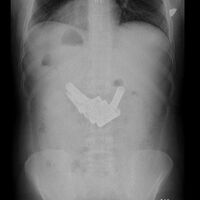

Huzursuz Barsak Sendromu diğer adıyla İrritabl Barsak Sendromu (İBS) toplumda yaklaşık 7 kişiden birinde görülen, altta yatan organik, yapısal bir barsak hastalığı olmadan meydana gelen, karında rahatsızlık hissi, düzensiz barsak hareketleri, belirgin derecede şişkinlik, zaman zaman ishal ve kabızlık ile kendini gösteren bir hastalıktır. İrritabl barsak sendromunda sindirim sistemi beklenilen şekilde çalışmaz, diğer bir adıyla tarif edildiği gibi hassaslaşmıştır. Hassas barsaklar yemekle veya bazen yemekten ilişkisiz olarak karında kramplara, şişliklere neden olabilir. Bazen de yemek sonrası acil tuvalet ihtiyacına neden olabilir. Gastroenteroloji Uzmanı Dr. Ayşe Kefeli konuyla ilgili bilgi verdi.